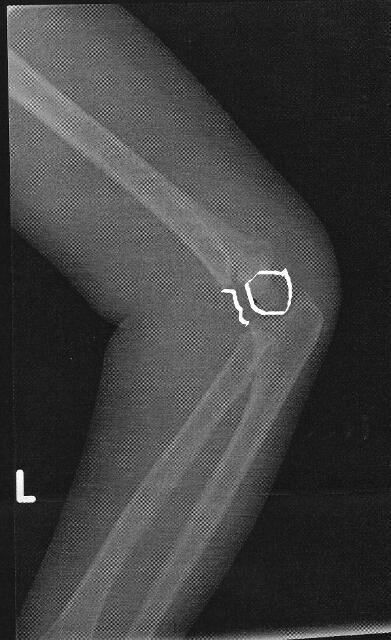

Hours later, after a seemingly endless time in the emergency room we got the diagnosis. A clear fracture of her humerus.

Note: The markings in the xray show the fracture and the resulting shift of the bone to the back.